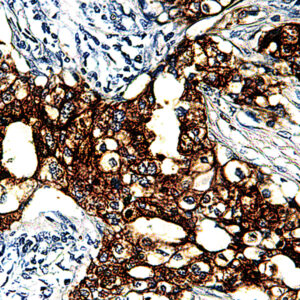

Anti-Cytokeratin 14

Keratins are intermediate filament proteins expressed by epithelial cells in cytoplasm. Mitotically active basal layers of most stratified squamous epithelia cells express 10% to 30% of their total protein as keratin. Cytokeratin 14 (CK14) is a 50-kDa keratin expressed in abundance in epidermal cells, basal cells, mesothelial cells, stratified epithelial cells, and myoepithelial cells in various tissues including prostate and breast. CK14 is helpful in the identification of breast cancer with basal phenotype